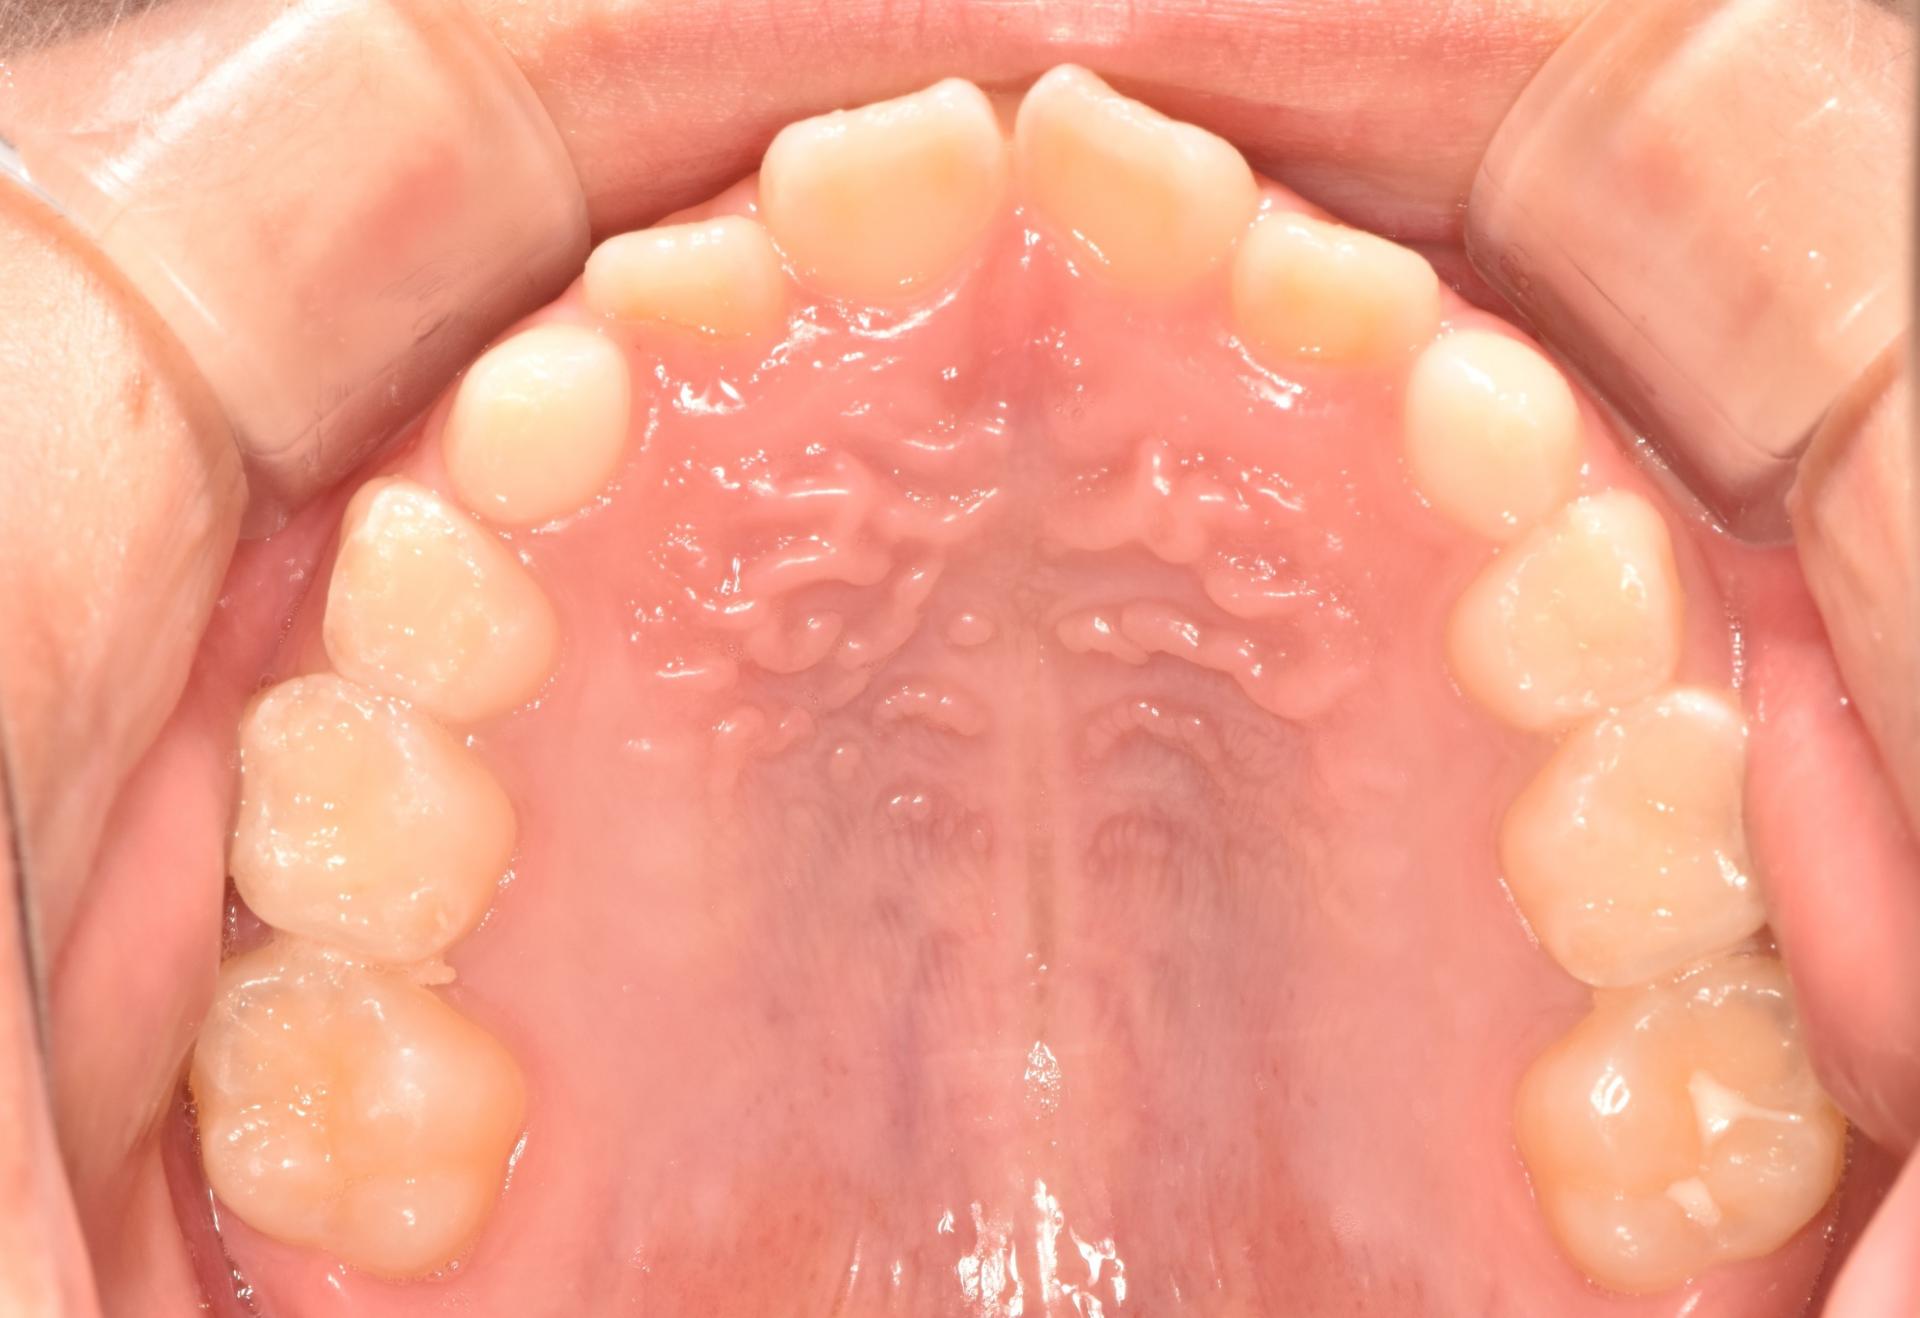

초진 사진입니다. 고르지 못한 앞니와 치아의 회전으로 인한 위아래 앞니의 부딪힘이 발생하고 있습니다. 또한 위아래 앞니의 뻐드러짐과 돌출이 보입니다.